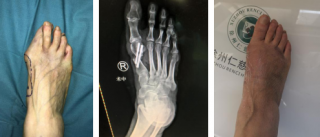

踇外翻俗称“大脚骨”,是一种常见的踇趾向足的外侧过度倾斜、第一跖骨内收的前足畸形,女性居多。

1、严重足部畸形,影响美观

如何治疗踇外翻?

第三代微创踇外翻矫正手术

仁慈足踝团队采用4毫米低频超声骨刀微创截骨,切口很小无需缝合;低频超声骨刀锋利、精准、自带注水降温,能更好地保护骨骼血运,使得截骨处更快愈合,手术基本无血渗出,完美修整踇外翻,术后第二天就能下地行走。